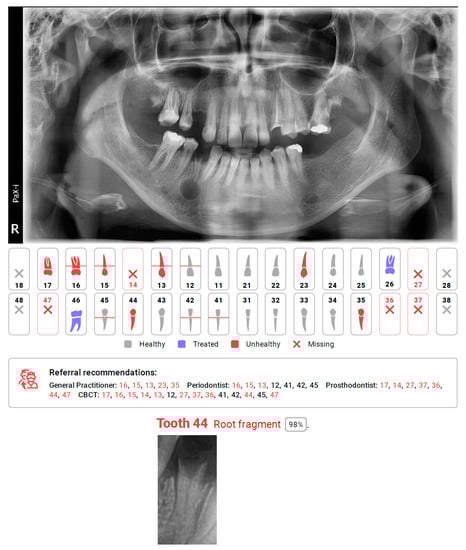

Figure 2.

Diagnocat report, with missing detection of cyst connected with tooth 44, and automating caption of tooth recognized as a root fragment.